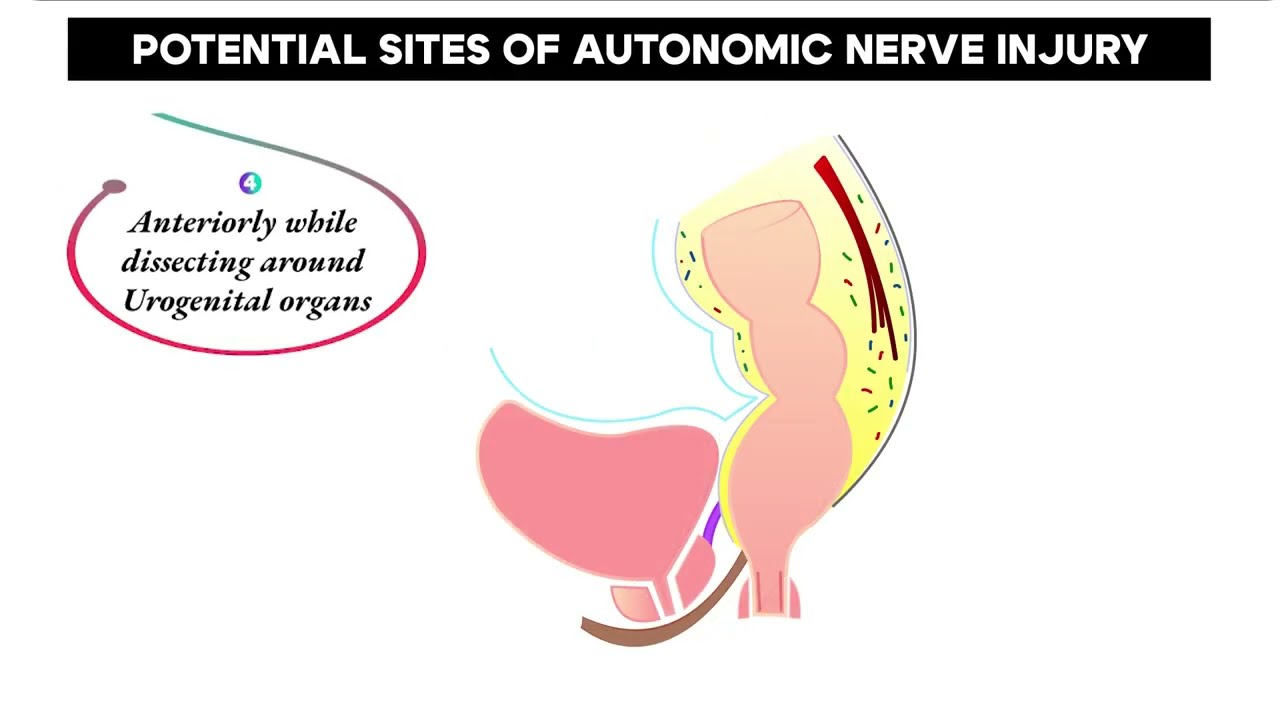

#295 AUTONOMIC NERVE PRESERVING ROBOTIC RECTAL SURGERY- ”RADICALITY WITH FUNCTIONALTY” Dr. K Agrawal